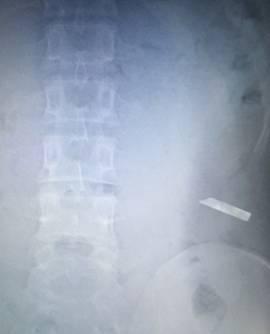

在今年上半年,我门诊上来了两个病人家属,带着一张腹部平片,问问我们这里能不能做取异物。我拿到片子看后又是一惊,竟然是一把裁纸刀的刀片。问是如何进肚子的,家属说是老人肚子疼痛难以忍受,一点一点插进去的。